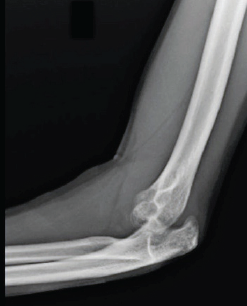

Surgical Treatment of Neglected Elbow Dislocation with the Box-loop Technique: A Case Report

Paulo Henrique Loureiro , Lucas Alves Domiciano Ferreira , Rafael Zonzini Veiga , Victor de Bulhões U. Sechin , Mário Lenza , Sérgio Rowinski

………………………………p.195-200